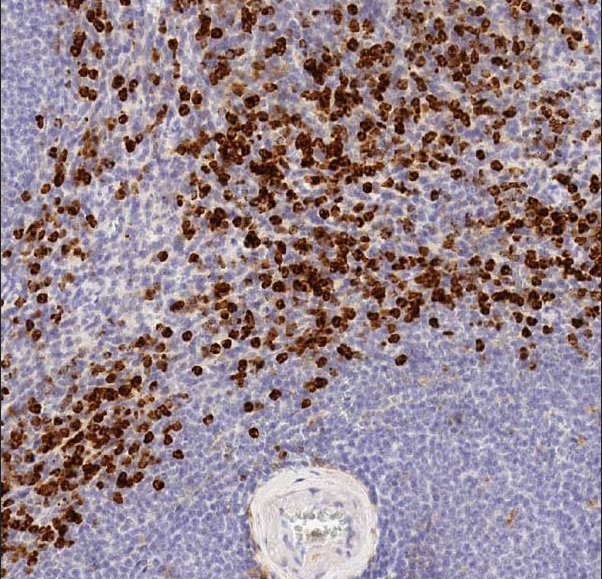

Integrin aM (ITGAM) is a subunit of a protein that forms giant cell antigen (Mac-1) or complement receptor 3 (CR3).ITGAM, also known as CR3A and differentiation antigen cluster molecule 11B (CD11b), is a common myeloid marker with a 50% positive expression rate in acute myeloid leukemias.Co-assay of CD117 and CD11b helps to distinguish acute promyelocytic leukemia (CD11b-positive expression) from cases of acute promyelocytic leukemia (CD11b-negative expression) from cases with restored benign proliferation (CD117-negative expression, CD11b-positive expression).

CD11b Antibody Reagent binds specifically to the CD11b molecular antigen. Immunohistochemistry kits containing CD11b Antibody Reagent are indicated for the precise diagnosis of Acute Myeloid Leukemia (AML), Chronic Myelomonocytic Leukemia (CMML), and Inflammatory/Immune Diseases.